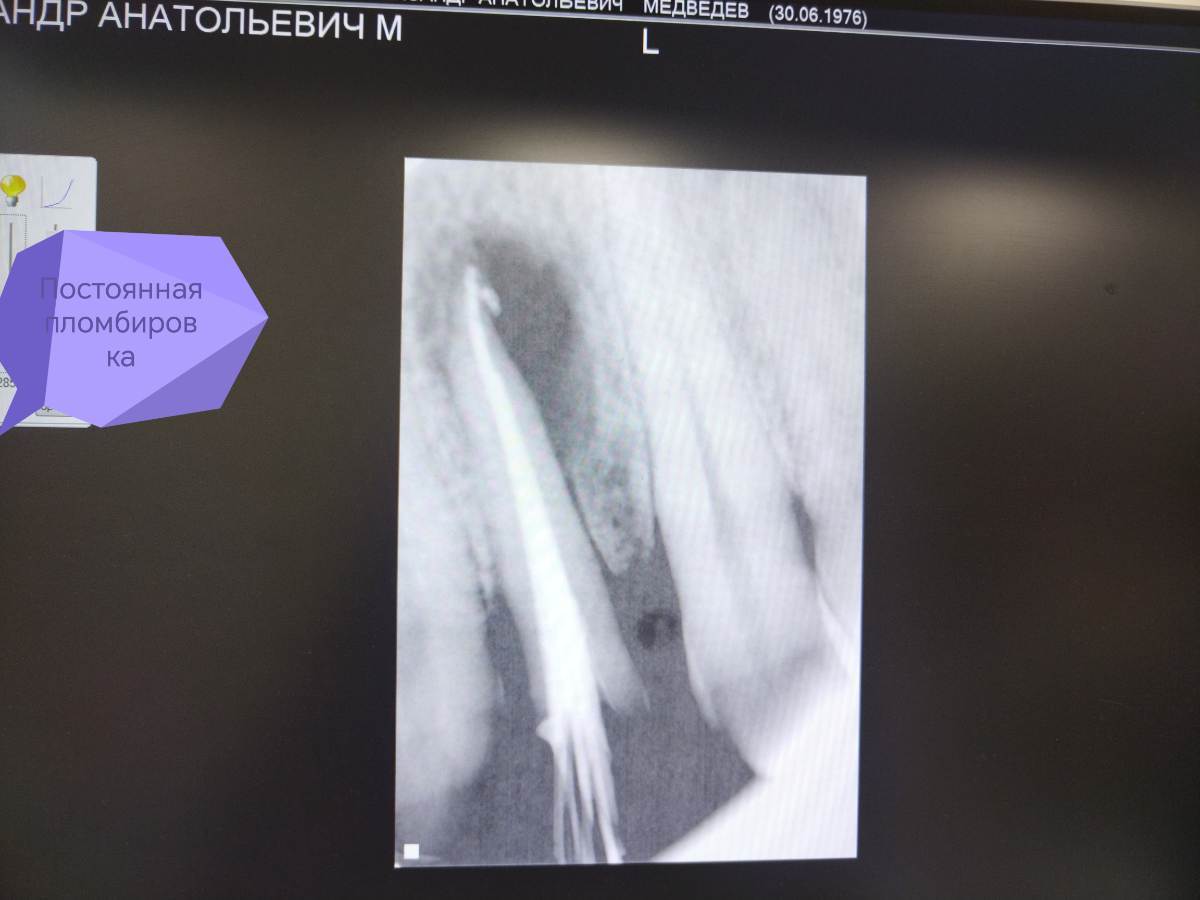

АВА2018 Опубликовано 28 декабря, 2025 Поделиться Опубликовано 28 декабря, 2025 Цитата Добрый вечер, коллеги 🙂Оцените, пожалуйста, качество пломбирования зуба 22 и есть ли перерасширение устьевой части канала.... Протокол работы: В 1 посещение-Механическая и медикаментозная обработка канала ручными к-файлами до 45 размера , промывание 3% раствором паркана, ЭДТА, активация эндоактиватором, вода. Изначальный размер канала 25 размер к -файла....Высушивание, получен экссудат в небольшом количестве. Временная пломбировка кальсептом на 2 недели. 2 посещение-Жалоб нет. Снятие пломбы, вымывание кальция из канала 3 % раствором паркана, водой дистиллированной. Долго не могла вымыть кальций из канала, при активации эндоактиватором выходили стружки кальция.... Постоянная пломбирование пастой Н+ с гуттаперчевыми штифтами методом латеральной конденсации. Пациенту придёт через 6 месяцев для контроля заживления.. Ссылка на комментарий

АВА2018 Опубликовано 28 декабря, 2025 Автор Поделиться Опубликовано 28 декабря, 2025 Скажите, пожалуйста, есть ли перерасширение цервикального дентина? Я работала без устьевика... Но на снимке отчётливо вижу перерасширение... Да и вообще проблема у меня с вымыванием кальция из каналов , я не могу понять, вымыла ли я его полностью, всё равно идёт белая стружка при активации. Я потом беру мастер-файл и н-файл по стенкам вожу и всё равно идёт белая стружка... Есть вообще ощущение, что я каналы перерасширяю.... Фанатизм мой до добра не доведёт... 😩Переживаю ща пациента.... Ну вот это перерасширение или просто ракурс такой? Ссылка на комментарий